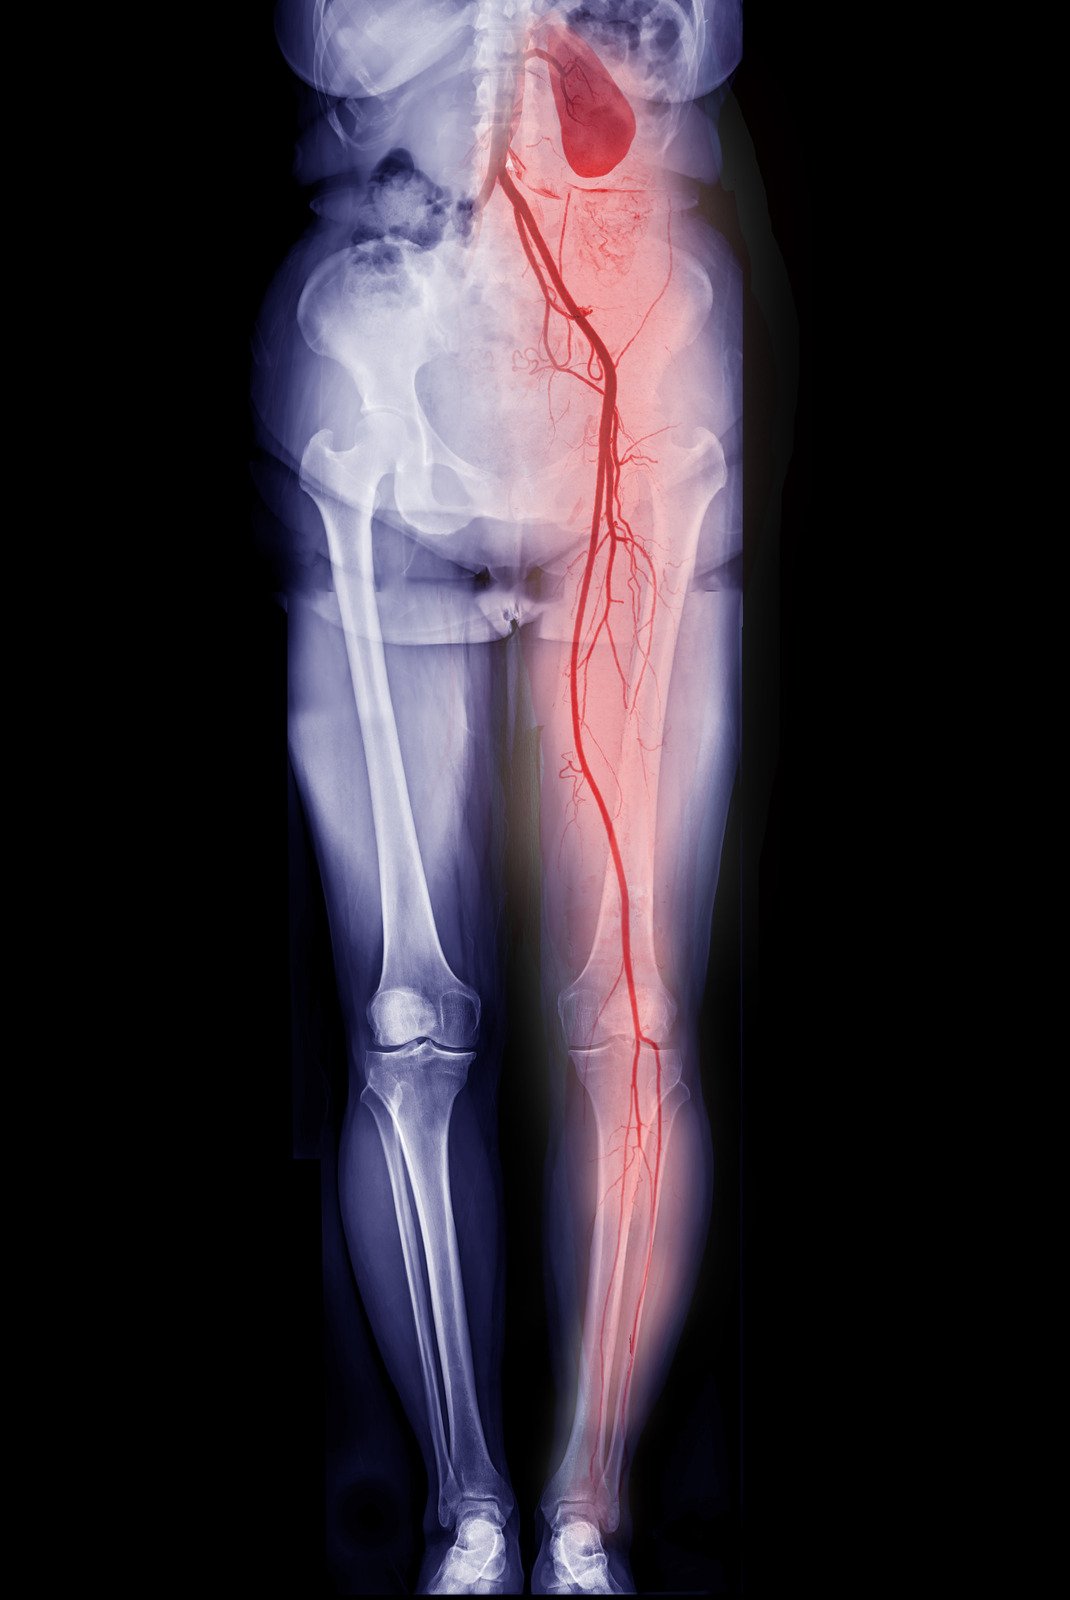

말초동맥질환(PAD, Peripheral Artery Disease) – 하지 혈관 협착 & 혈류 장애

말초동맥질환(PAD, Peripheral Artery Disease) 는 동맥이 좁아지거나 막혀서 다리로 가는 혈류가 감소하는 질환입니다.

✅ 3) CT 또는 MRI 혈관조영술 (CTA/MRA)

✔ 동맥이 좁아진 정도 & 위치를 정확하게 확인하는 검사

📌 혈관이 심하게 좁아진 경우, 혈관 확장 시술(스텐트 시술) 여부를 결정하기 위해 시행됩니다.